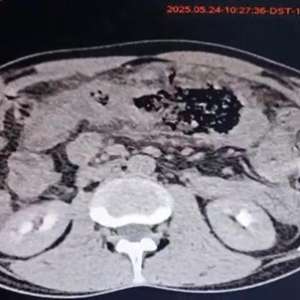

Мужчина, 60 лет

Хронические заболевания: артериальная гипертензия, биполярное расстройство.

Обратился с жалобами на нарушение мочеиспускания к урологу, была назначена МРТ.

По данным МРТ обнаружены многочисленные микрокисты в корковом и мозговом веществе обеих почек (рис. A, вид в аксиальной плоскости; рис. B, вид в коронарной плоскости).